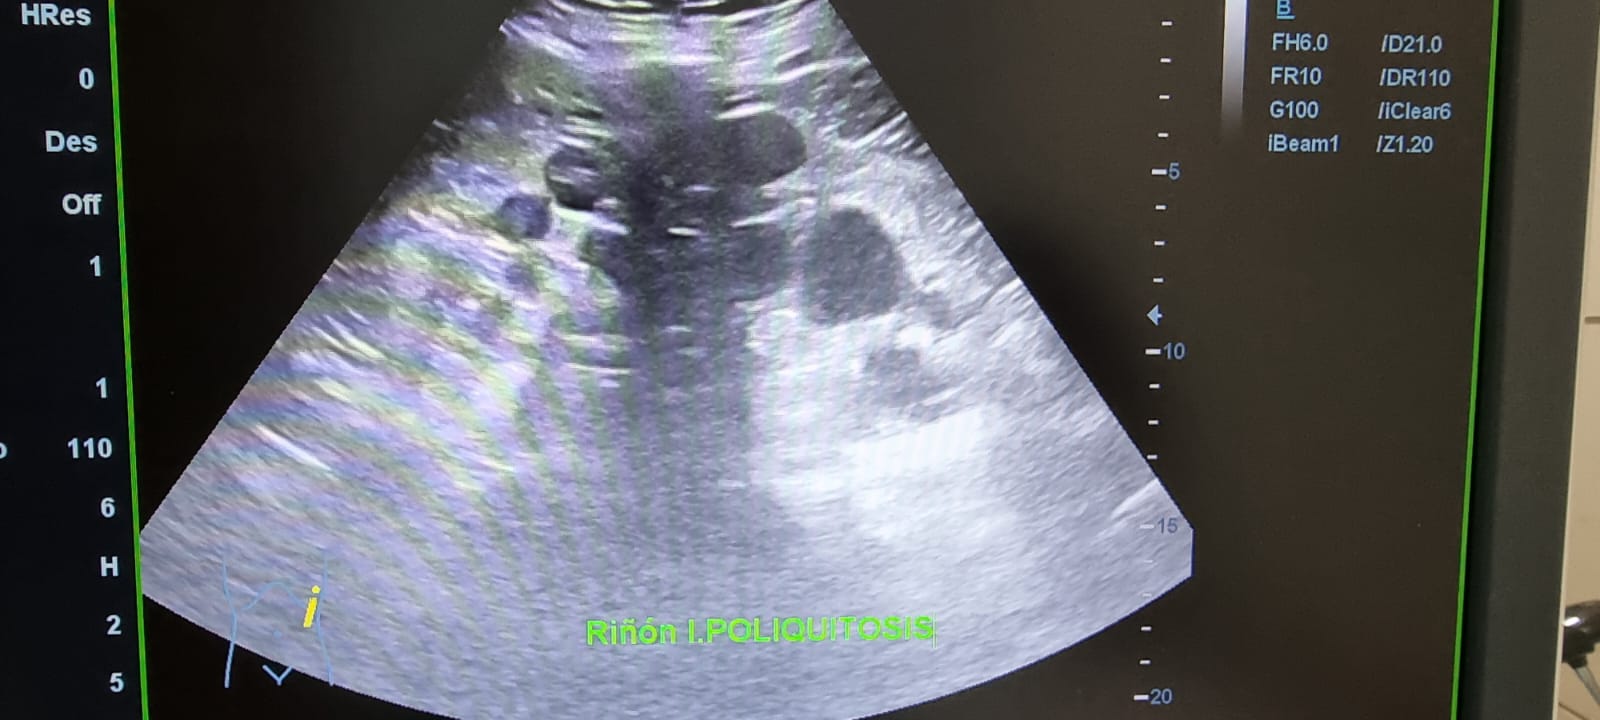

Ecografía abdominal: Hepatomegalia esteatósica difusa leve con múltiples imágenes anecoicas con refuerzo posterior, sin vascularización, compatible con poliquistosis. Riñón derecho con múltiples imágenes anecoicas en polo superior e inferior con refuerzo posterior. Sin signos de uropatía obstructiva. Riñón izquierdo con presencia de múltiples imágenes anecoicas compatibles con poliquistosis.